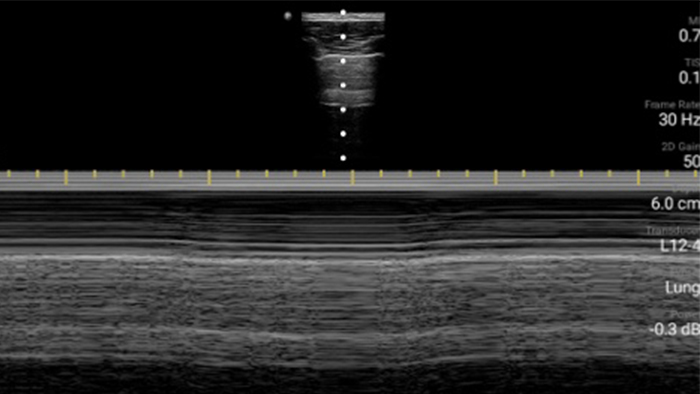

Breathe easier with Lumify

Lumify can help assess patients faster and improve accuracy when diagnosing common causes of dyspnea and other lung conditions.

Lumify L12-4 broadband linear array transducer